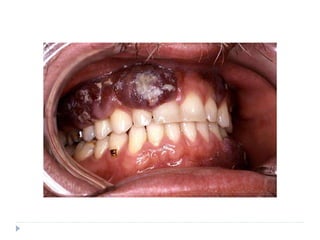

CLINICAL PRESENTATION

 AIDS related Kaposi’s sarcoma

 Early sign of AIDS

 Multiple lesions of skin and mucosa

 70% of patients demonstrate oral lesions; in 22%,oral

lesions are the first manifestation

 Hard palate, gingiva and tongue are commonly affected

 Palatal and gingival lesions invade bone and cause

tooth mobility

 Present as brown or reddish purple macular lesions

that do not blanch on pressure

 Later macules develop into plaques or nodules

 Pain, bleeding and necrosis are seen